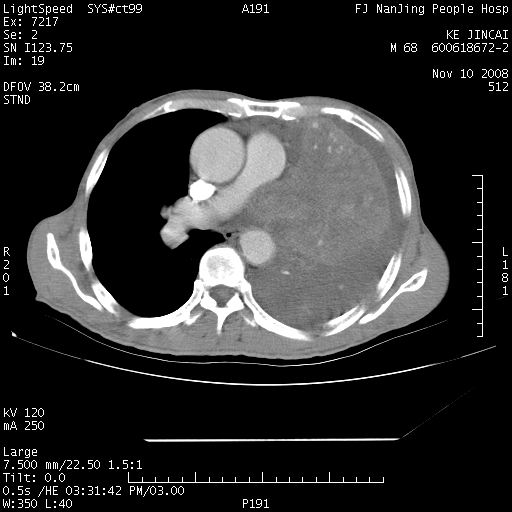

是个很有看头的病例,咋人气那么不旺?没多少人兴趣呢?这个病例几大怪:1   恶性肿瘤侵犯心肌左房怪,心肌一般不会被恶性肿瘤侵犯吧?2   左下肺均匀实变怪,内无含气,有别一般不张实变,含气肺泡完全为液体取代,而非一般不张实变的肺萎陷,冷不丁还以为是肿大的脾脏3   肿瘤本身怪,像tb肺不张4   这么有看头的病例没人气怪。呵呵。

左肺恶性肿瘤侵犯肺动脉,左心房内瘤栓,胸膜转移。